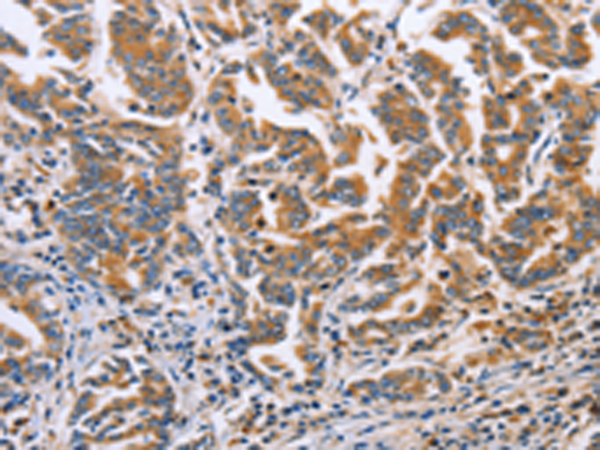

分类: 科研抗体货号: P07954别名: MAY1; PKCD; nPKC-delta应用: WB,IHC反应种属: Human, Mouse, Rat